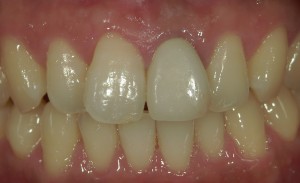

術前

術後

かぶせものをとると中はこのように傷んでいることが多く、この方の場合も歯根がかなり傷んでしまっていることがわかります。